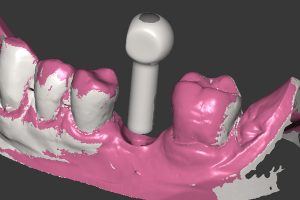

- Ryc. 19_Wirtualny obraz planowanego łącznika dla systemu Atlantis C/X w oprogramowaniu ATLANTIS-VAD.

- Ryc. 20_Projekt łącznika Atlantis w stosunku do zębów przeciwstawnych widoczny w oprogramowaniu ATLANTIS-VAD.

Po zamontowaniu tzw. skan lokatorów i zeskanowaniu modelu, wypełniany jest formularz zamówienia na łącznik. Zawiera on wszystkie niezbędne informacje dotyczące sposobu wykonania łącznika zgodnie z życzeniem zamawiającego takie, jak: rodzaj materiału, kompresja tkanek miękkich, profil wyłaniania, angulacja, wysokość okluzyjna, głębokość posadowienia poddziąsłowo stopnia dla korony itp. Następnie formularz ten (tzw. Atlantis WebOrder) łącznie ze skanami przesyłany jest do Centrum Projektowania i Frezowania Atlantis. W odpowiedzi na zamówienie otrzymujemy wirtualny projekt łącznika do akceptacji w programie Atlantis VAD. W zależności od tego, czy projekt spełnia nasze oczekiwania, czy też wymaga zmian, do Centrum Projektowania wysyłana jest określona informacja. Po ostatecznym za- akceptowaniu projektu łącznika, zamówienie otrzymuje status realizacji i łącznik przekazy- wany jest do produkcji. Po kilku dniach łącznik trafia do laboratorium, gdzie jest sprawdzany na modelach gipsowych i odsyłany do kontroli klinicznej.